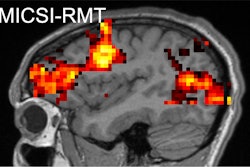

Parkinson's disease can manifest as tremors, slowness of movement, or rigidity, and its symptoms worsen over time, according to the RSNA. Basaia's group explored whether a "connectome map" of structural and functional brain connections could predict Parkinson's disease progression via a study that included 86 patients with mild disease (mean age, 60 years) and 60 healthy controls (mean age, 62 years). All participants underwent 3D T1-weighted brain MR imaging; the team assessed the extent of regional gray matter atrophy at baseline and every year for three years.

The investigators constructed the connectome map using diffusion tensor imaging (DTI) and resting-state functional MRI (fMRI) data from the study's healthy controls. They defined disease exposure indexes -- that is, directories of the pathology of each brain region -- by evaluating the structural or functional connectivity of all the connected regions in the healthy connectome and the severity of atrophy of the connected regions in participants with Parkinson's. Finally, the authors assessed any correlations between structural and functional disease exposure indexes of each gray matter region at one- or two-year follow-up and atrophy progression at two- or three-year follow-up.